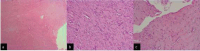

The authors present a case of fibroma of the tendon sheath with intra-articular location in the knee, more specifically in the infrapatellar fat; with this specific location, this is the fourth case described of an entity that rarely affects large joints. Clinical and epidemiological aspects, but especially the imaging findings on magnetic resonance imaging scans, are essential for the differential and definitive diagnosis, which was nevertheless established only after a histological study of the excised mass by miniarthrotomy.